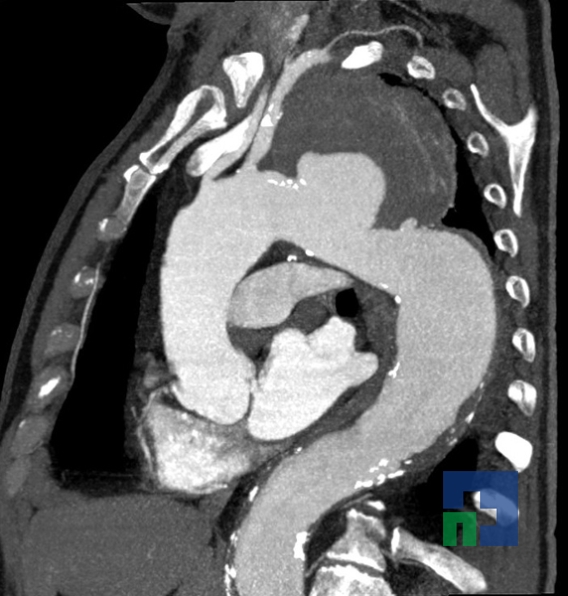

- Diagnosticul edemului cerebral, a contuziei cerebrale, a leziunilor axonale difuze edematoase/hemoragice, a dilacerării cerebrale, a hematomului intraparenchimatos posttraumatic, a hematoamelor subdurale/extradurale (acute, subacute, cronice), a hemoragiei intraventriculare, a hemoragiei subarahnoidiene